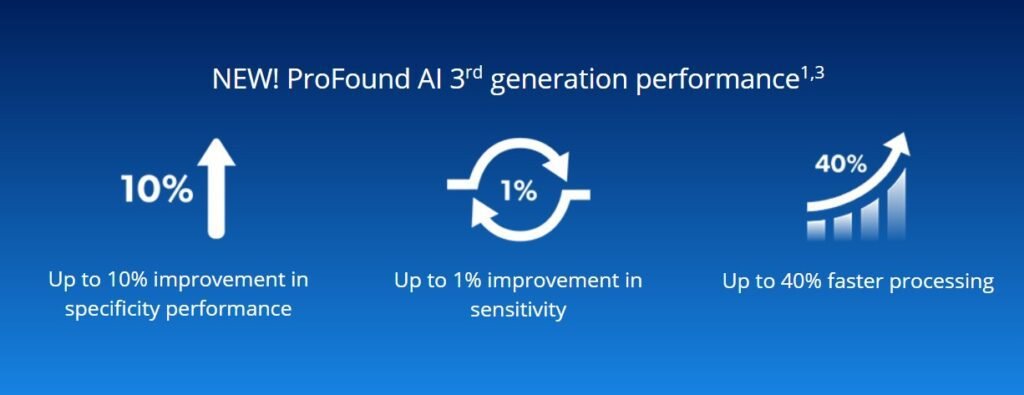

3.Compared to previous versions of the software, the ProFound AI 3.0 algorithm offers up to a 10% improvement in specificity performance, up to 1% improvement in sensitivity, and up to 40% faster processing on the new PowerLook platform.